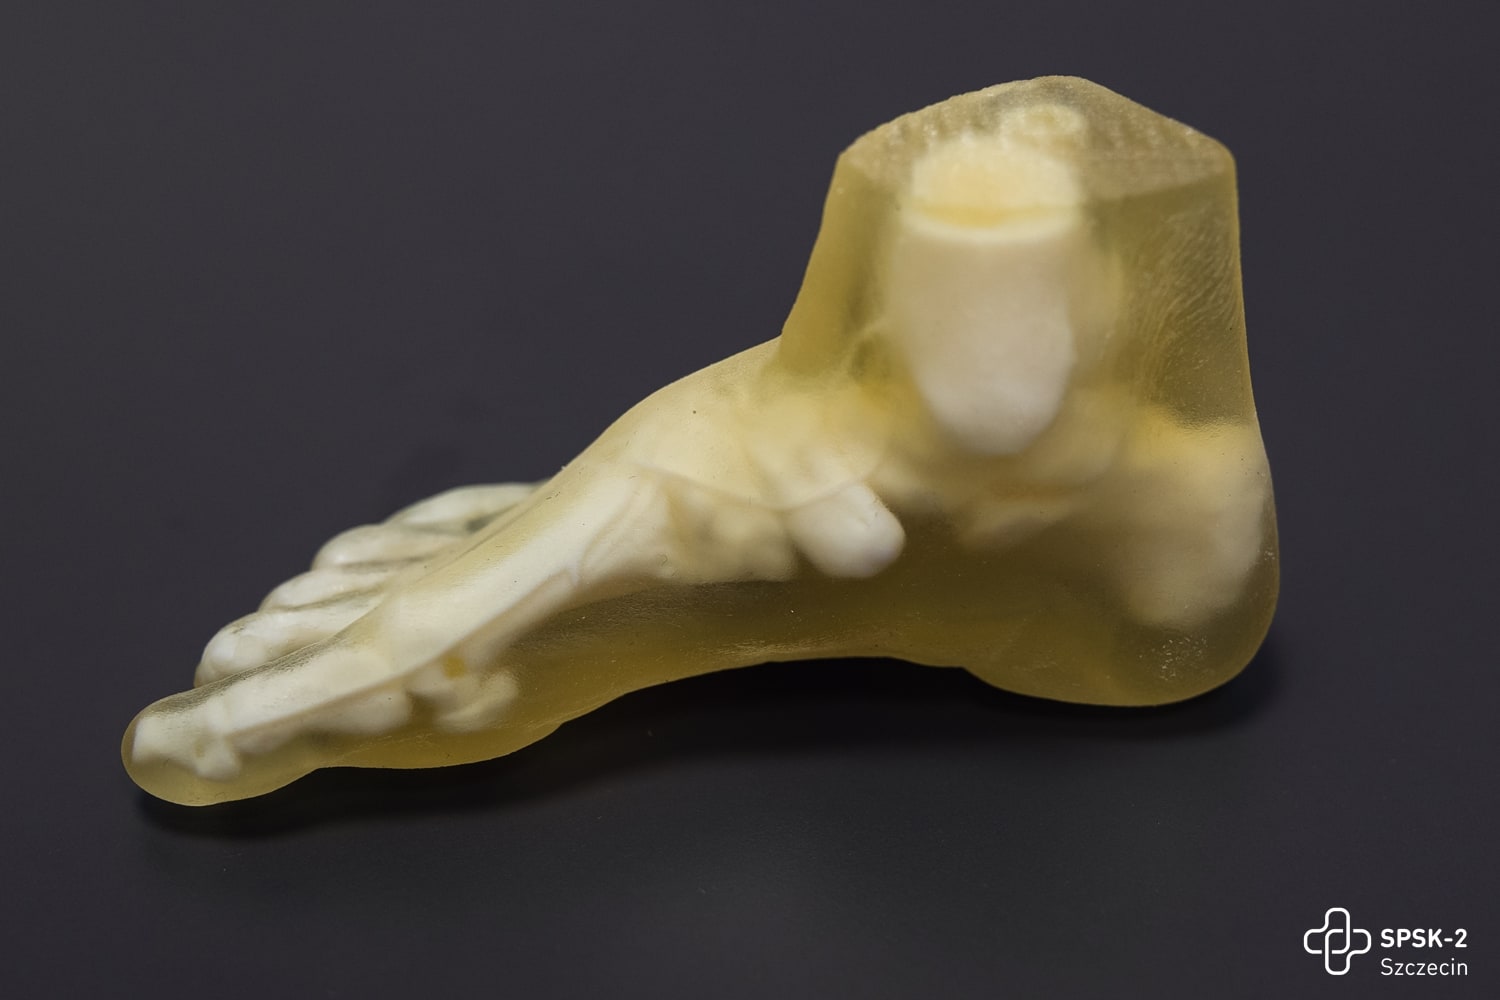

Oprócz badań USG chętni mogli zaznajomić się z najnowszymi metodami leczenia tętniaków aorty, obejrzeć filmy, w których nasi chirurdzy naczyniowi opowiadają o zagrożeniach chorobami naczyniowymi, zobaczyć na własne oczy czym jest tętniak i jak wygląda, obejrzeć wydrukowane w Ośrodku Technologii Medycznych 3D naszego szpitala modele organów człowieka, oraz poczuć się jak chirurg podczas operacji i dzięki goglom Hololens i wyświetlanemu w nich obrazowi rozszerzonej rzeczywistości ponawigować obrazem tomografii komputerowej i dokładnie obejrzeć struktury anatomiczne człowieka.

Jedyny w kraju Ośrodek Medycznych Technologii 3D otwarty!

Dostępne na co dzień dwuwymiarowe wyniki badań chorego – tomografia komputerowa, czy rezonans magnetyczny, to lata temu był skok w przyszłość. Dziś to już trochę za mało. Trzeci wymiar obrazu struktur anatomicznych chorego to ten element, który niezwykle ułatwia pracę lekarzowi. By stworzyć trójwymiarowy obraz z pomocą przychodzi druk 3D oraz hologramy.

W Ośrodku Medycznych Technologii 3D (OMT3D) powstać będą trójwymiarowe modele organów pacjentów – prawidłowe lub ze zmianami patologicznymi. Wydruk będzie powstawał w najnowszej generacji drukarkach 3D, umożliwiających druk nie tylko dowolnych struktur anatomicznych pacjenta z ich patologiami, ale odwzorowujących także kolory, strukturę, giętkość i twardość prawdziwych organów i tkanek. A dzięki goglom Hololens2, operujący lekarz będzie w powietrzu nawigował hologramem, przedstawiającym zdjęcia diagnostyki obrazowej pacjenta.

Wyposażenie OMT3D:

Drukarki

- najbardziej zaawansowane technologicznie, do zastosowań w medycynie

- możliwość druku z 6 różnych materiałów w trakcie jednego zadania!

- dzięki temu drukowane są modele wielomateriałowych, z… 500 000 barw

- ustawienia pozwalają rozszerzyć właściwości fizyczne standardowych materiałów i uzyskać odpowiedni stopień ich twardości,

- a także uzyskać odpowiedni obraz i strukturę stanu chorobowego – np. zwłóknienia tkanek czy zwapnienia kości

- olbrzymia komora drukowania (490 mm x 390 mm x 200 mm) pozwala wytwarzać całe organy bez konieczności łączenia ich poszczególnych elementów (np. cała czaszka w jej naturalnych rozmiarach.

Materiały

- od najbardziej miękkich (np. do druku tkanki serca), elastycznych,

- ale poddających się różnym „procedurom medycznym”, np. wprowadzaniu cewników,

- przez twarde, ale elastyczne i odporne na wielokrotne zginanie,

- do twardych, naśladujących strukturę kości, na których także można przeprowadzać „operacje” – ciąć, wiercić,

- aż po takie, które nie przepuszczają promieni roentgenowskich.